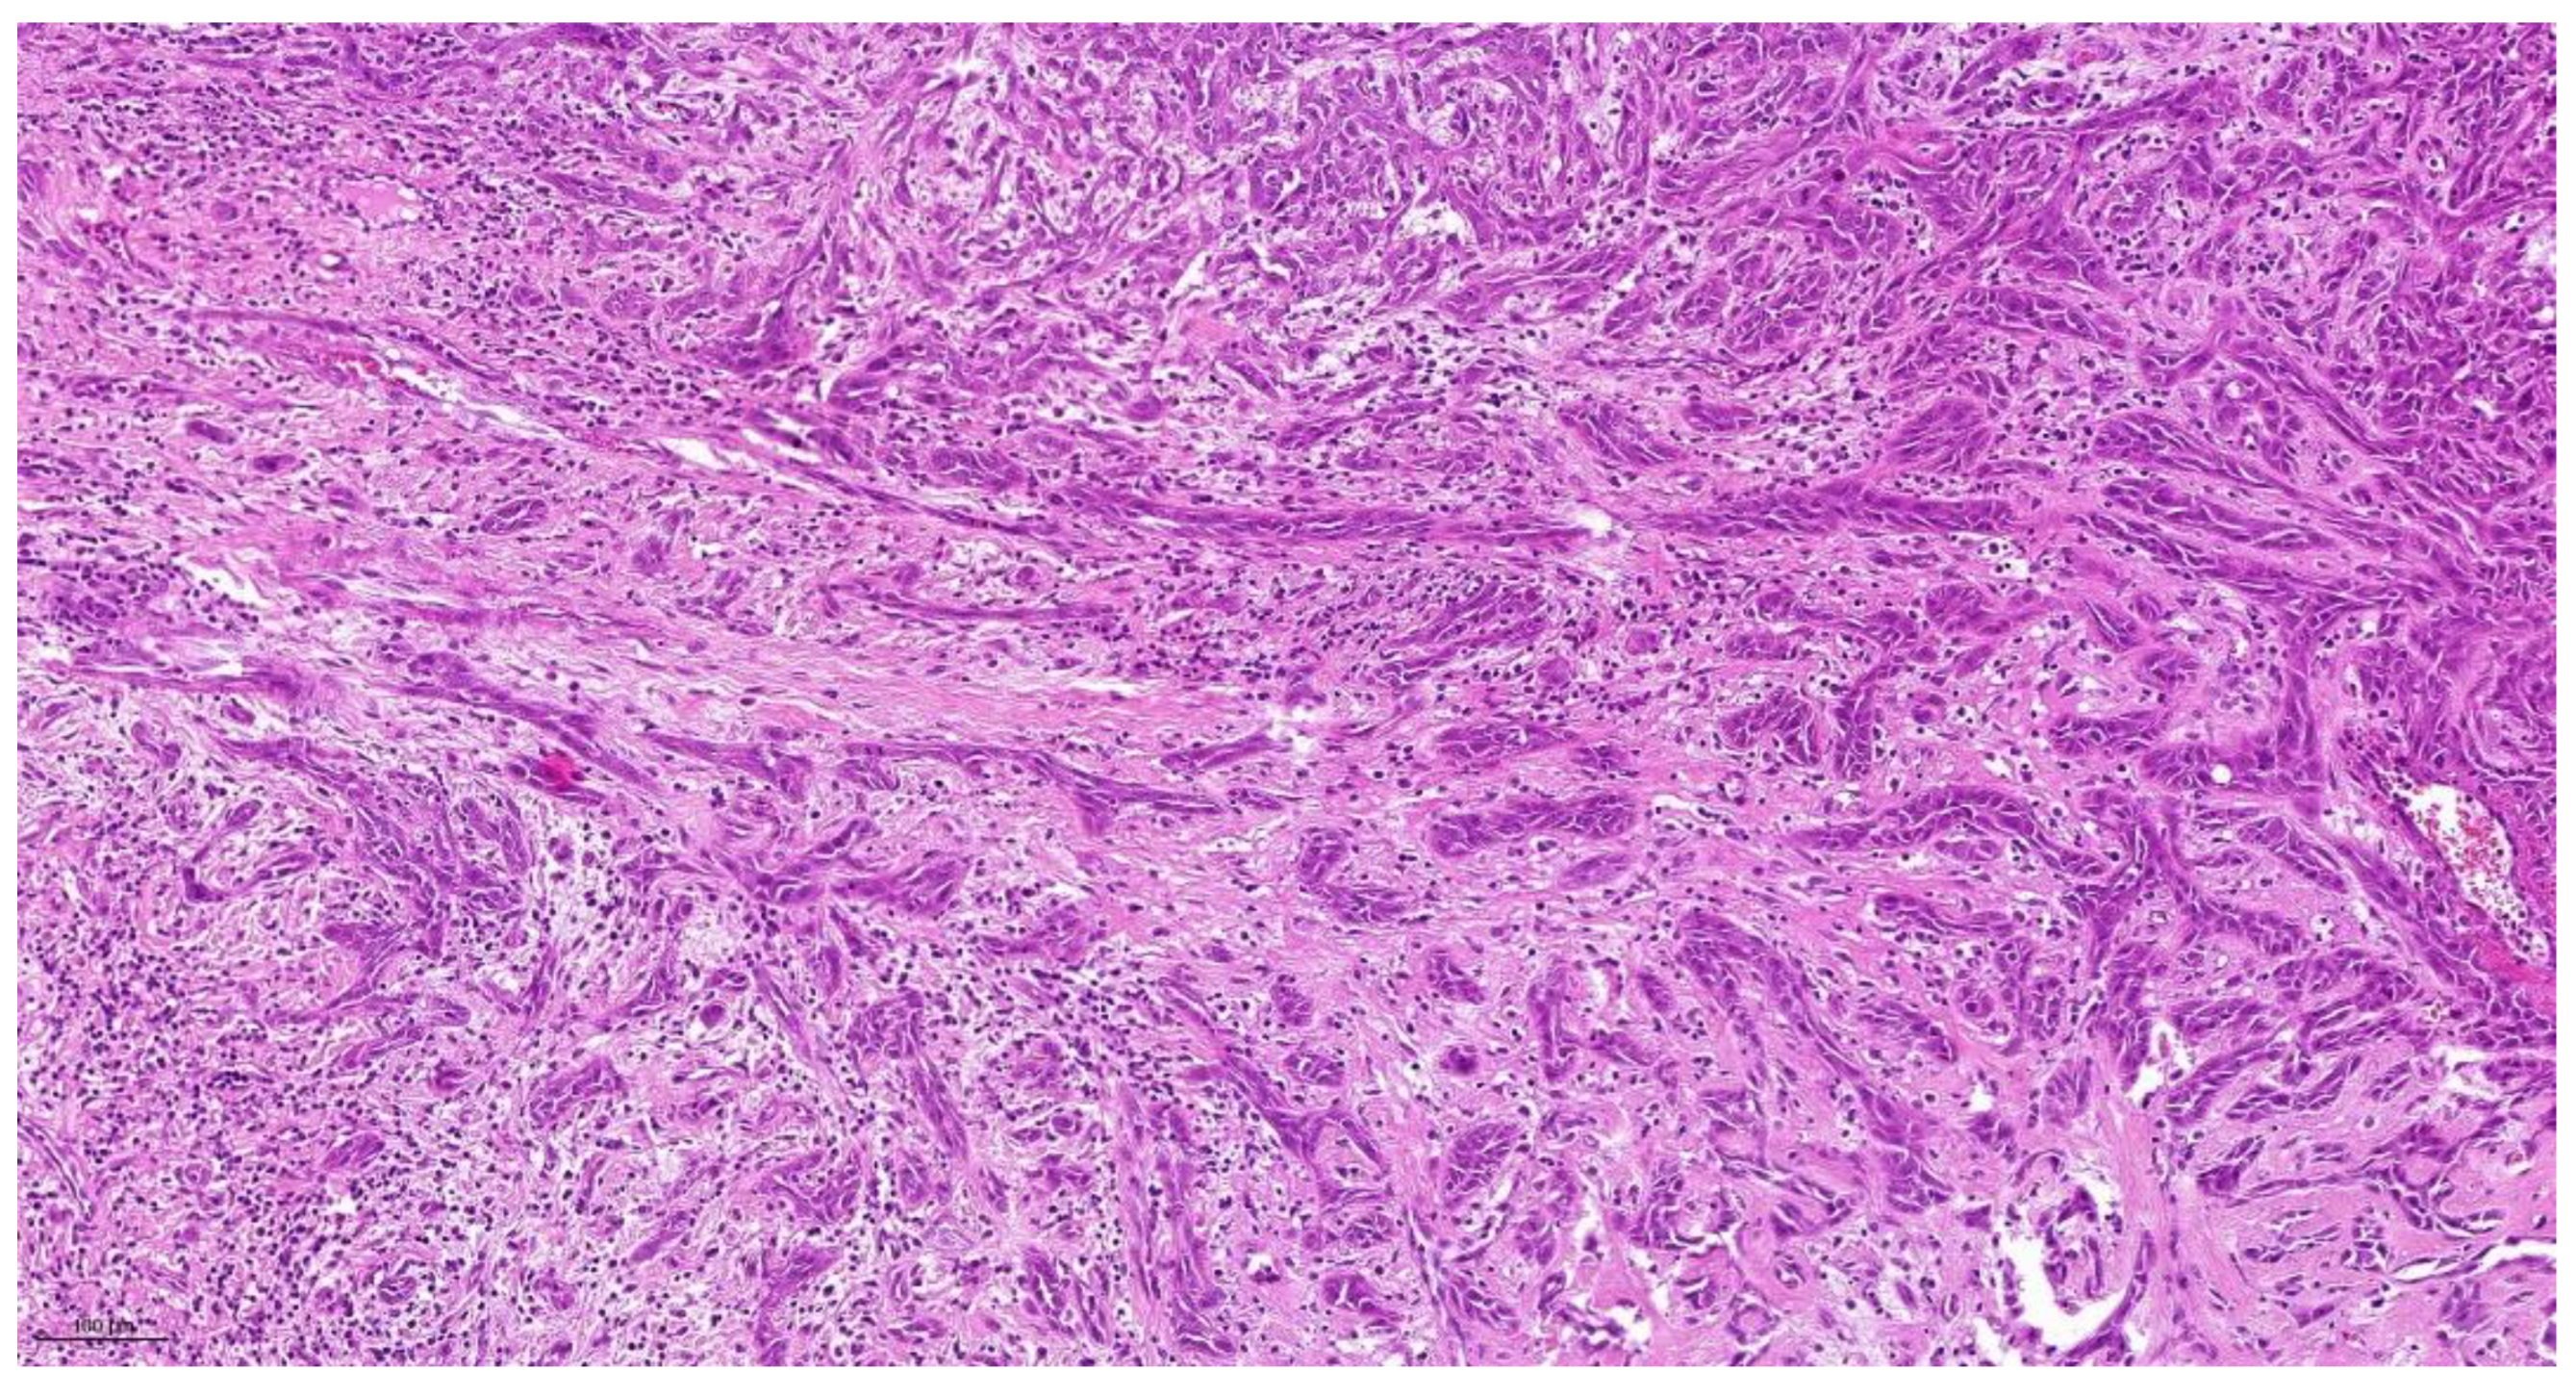

| Tumor Budding * (TB) | No tumor budding | Score 1 |

| 1–5 tumor buds/HPF | Score 2 | |

| >5 tumor buds/HPF | Score 3 | |

| Cell Nest Size (CNS) | >15 cells per nest 5–15 cells per nest 2–4 cells per nest | Score 1 Score 2 Score 3 |

| single cell invasion | Score 4 | |

| Cellular Dissociation Grade (CDG) | Sum TB + CNS = 2–3 Sum TB + CNS = 4–5 | CDG-1 CDG-2 |

| Sum TB + CNS = 6–7 | CDG-3 |